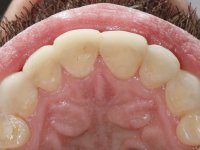

Paciente do sexo masculino, com 36 anos, não fumador. Fez tratamento ortodôntico e reabilitou esteticamente o sector anterior com restaurações em resina composta. As restaurações apresentavam um aumento vertical médio de 2 mm em relação o bordo incisal. Apresentavam-se esteticamente satisfatórias, mas com algumas fraturas incisais. O dente 1.5 apresentava um processo apical e o dente 2.6 apresentava tratamento endodôntico e uma lesão endo-periodontal. No maxilar inferior no local do dente 3.5 apresentava um implante com uma coroa aparafusada e o dente 8.5 ainda estava presente em boca com agenesia do dente 4.5. O paciente apresentava uma ligeira perda da dimensão vertical da oclusão provavelmente associada a um visível desgaste das superfícies oclusais. O periodonto era espesso e apresentava uma excelente higiene oral.

Realizado o diagnóstico e tomada a decisão quanto ao tratamento a executar, tornou-se importante definir qual a sequência de trabalho a adotar no sentido de conseguir a reabilitação da D.V.O. (V.D.O), de forma progressiva e equilibrada. Na primeira fase fez-se uma pré-impressão da arcada inferior com silicone tipo “putty” e em seguida realizou-se o preparo dentário de todo o sector posterior. O preparo para os overlays foi feito coronalmente à linha amelo cementaria no sentido de ser o mais conservador possível. A impressão foi feita com técnica de dupla mistura após afastamento gengival realizado com pasta de caulino. A provisória foi realizada com resina composta de polimerização dual. Em laboratório foram realizados os overlays após se ter aberto ligeiramente (1,5mm) a D.V.O. nos modelos montados em articulador semi-ajustável. Simultaneamente o sector antero-inferior foi encerado no sentido de acompanhar este aumento da D.V.O. Também foi confecionada uma chave de silicone translucido para posterior confeção dos provisórios antero-inferiores. Em boca foi primeiro realizada a provisionalização dos dentes anteriores utilizando resina composta previamente aquecida após preparação das superfícies dentárias para a adesão. Foi colocado o dique de borracha para promover o isolamento absoluto e posteriormente foram colados os overlays. Em laboratório foi realizada nova chave de silicone para confecionar os provisórios antero-superiores. Seguidamente em boca foram preparados os seis dentes antero-superiores após colocação do fio de afastamento gengival. Feita a preparação adequada das superfícies dentárias foi realizada a impressão com técnica de dupla mistura e a respetiva provisória. Em laboratório foram confecionadas 6 facetas feldespáticas num modelo de trabalho tipo “Geller”. A provisória foi removida e as facetas foram coladas em boca utilizando um isolamento relativo competente. Esta opção foi tomada em virtude de uma prévia experiencia negativa com a colocação do dique de borracha na mandibula. Após a colagem dos laminados antero-superiores foram dadas 12 semanas para avaliar a adaptação do paciente à nova situação e então iniciar a confeção das facetas antero-inferiores. Após colocação do fio de afastamento gengival. foram feitos os preparos dentários adequados e em seguida foi feita a impressão. Também foi feita a preparação do dente 3.4 que, entretanto, tinha sofrido uma fratura do overlay. As facetas e a restauração do 3.4 foram realizadas num modelo de trabalho tipo “Geller”. Após remoção da provisória, as facetas foram coladas em boca, utilizando um isolamento relativo pelas razões apontadas anteriormente. Após colocação do trabalho o paciente foi reabilitado por outros colegas com um implante na zona do 2.6 e substituição da coroa aparafusada sobre o implante colocado no local do 3.5. Posteriormente surgiram fraturas nos overlays dos dentes 4.7 e 3.7 que foram reabilitados com overlays em Zr.